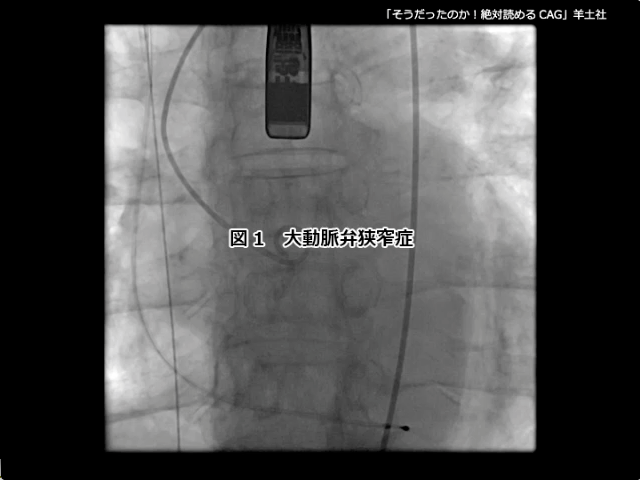

そうだったのか! 絶対読めるCAG【付録動画サンプル】